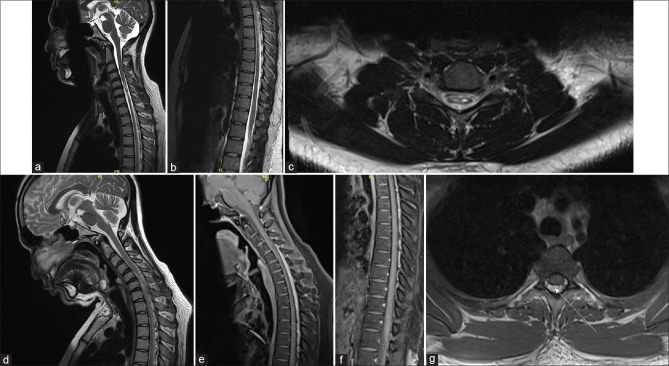

背景和目的:平山病(Hirayama disease, HD)是一种颈椎屈曲引起的压缩性脊髓病。典型的是,在颈部屈曲时,在颈椎水平有向前移位和硬脑膜囊与椎板的附着丢失。然而,硬脑膜脱离(DD)的程度尚未被仔细研究。我们进行这项研究是为了了解DD在HD中的程度。方法:我们对2015年至2023年评估的HD患者进行了回顾性研究。选择扩展到颈椎以外的DD患者,并对其临床和影像学特征进行研究。结果:在一组210例HD患者中,有132例(62.8%)患者被确定为超过颈椎的DD。平均发病年龄为18.09±2.3年(13-26岁),平均病程为38.63±39.9个月。50%的患者有近端和远端受累,33%和17%的患者分别有远端和近端受累。3例患者腿部消瘦。96.9%的患者存在脊髓萎缩,从C5延伸到C7。所有患者均有明显的硬膜外脱离和硬膜外静脉丛扩张。DD从C2椎体延伸至D10椎体。87%的病例DD的颅脑范围为C2至C4, 84%的病例DD的尾侧范围为D1-D5, 2例扩展至D10。结论:HD频谱在表型和放射学上继续演变。在很大比例的患者中,病理生理机制和DD延伸到颈椎以外。这使得在成像时覆盖较长的脊柱部分变得很重要。这可能对患者的治疗有影响,特别是那些孤立下肢受累的患者。

Results: One hundred and thirty-two (62.8%) patients were identified to have DD beyond the cervical spine in a cohort of 210 HD patients. The mean age at onset and duration were 18.09 ± 2.3 years (13-26) and 38.63 ± 39.9 months, respectively. Proximo-distal involvement was noted in 50% of patients, while 33% and 17% of patients had isolated distal and proximal involvement, respectively. Wasted legs were observed in three patients. Cord atrophy was present in 96.9% of patients, extending from C5 to C7. Epidural detachment and engorgement of posterior epidural venous plexus were evident in all. DD extended from C2 to D10 vertebral level. The cranial extent of DD was from C2 to C4 in 87% of cases, and the caudal extent was D1-D5 in 84% of cases, extending up to D10 in two cases.

Conclusions: The HD spectrum continues to evolve phenotypically and radiologically. The pathophysiological mechanisms and DD extend beyond the cervical spine in a large proportion of patients. This makes it important to cover a longer part of the spine during imaging. This may have implications on the management of patients, particularly those with isolated lower limb involvement.